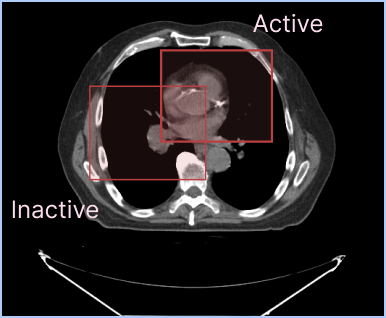

As you see in the picture above, you can display two different labelmaps at the same time. Default configuration for active segmentation representation is to have a higher outline width value than the inactive segmentation representation in order to make the active segmentation representation more visible.